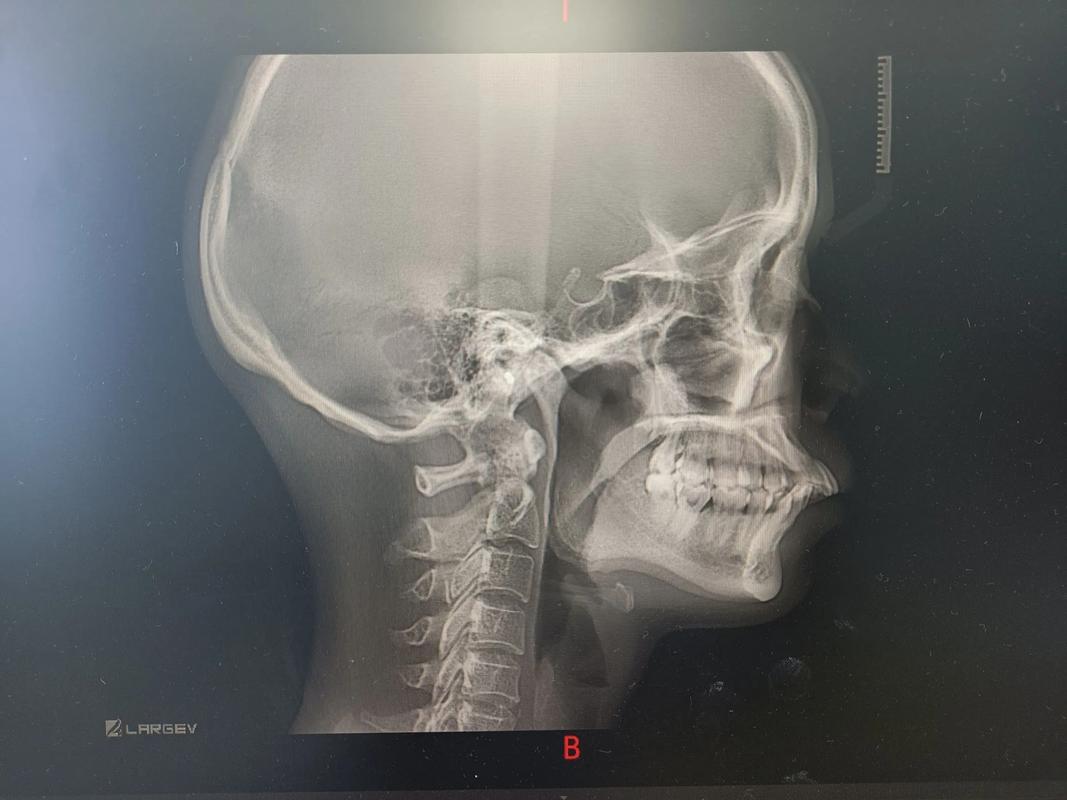

头颅侧位片:颌面关系的“三维透视镜”

头颅侧位片通过标记颅骨、颌骨、牙齿及软组织的解剖点,分析上下颌骨的相对位置、牙齿与颌骨的协调性,三个月时,核心评估指标包括:

- 骨骼变化:对于成人骨性正畸或生长改良治疗,观察上下颌骨(如上颌骨A点、下颌骨B点)是否出现轻微位移;青少年患者则需关注髁突(下颌骨与颅骨连接处)是否有改建迹象,判断生长潜力是否被充分利用。

- 牙齿倾斜度:测量上下中切牙的长轴与颌平面的角度(如U1-NA角),若初期使用摇椅形弓丝,三个月时上中切牙应向舌侧倾斜,覆盖减小;若角度变化不明显,可能需调整弓丝力度或增加牵引。

- 软组织侧貌:观察鼻唇角、唇突度等指标,例如上颌前牙回收后,上唇突度应随之改善,侧貌更协调。